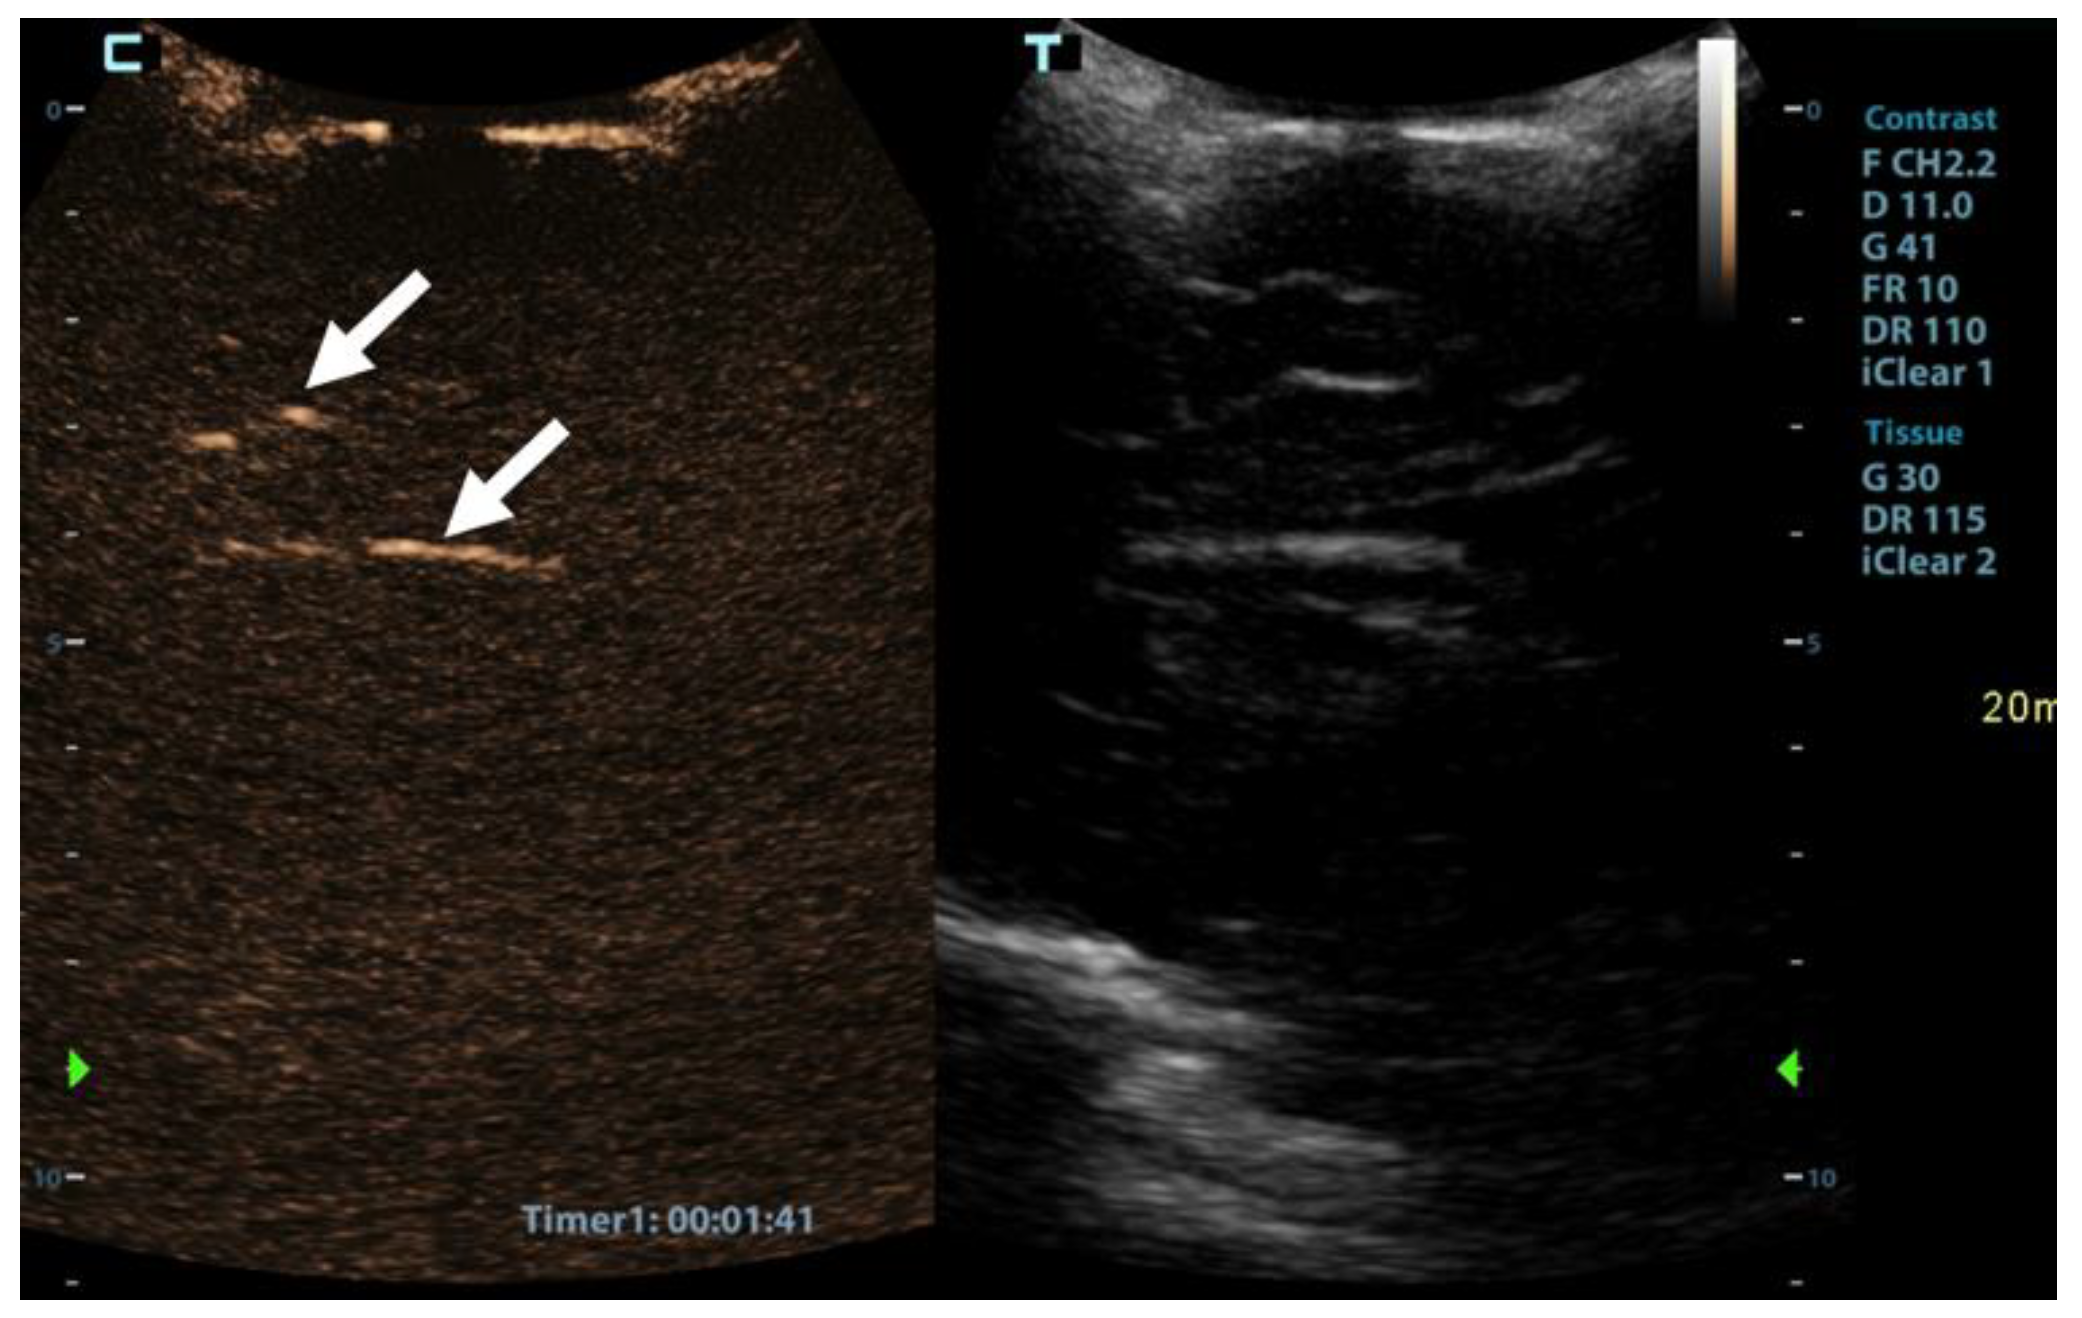

After the US examination, cerebral perfusion scintigraphy was performed as a widely accepted ancillary imaging test for brain death confirmation. The perfusion scintigraphy showed no accumulation of the radionuclides in the brain or the brainstem (Figure 4).

Figure 4. Radionuclide brain scan in the 1-year-old infant. Brain scintigraphy shows the absence of cerebral perfusion in supratentorial and infratentorial areas consistent with the diagnosis of brain death.